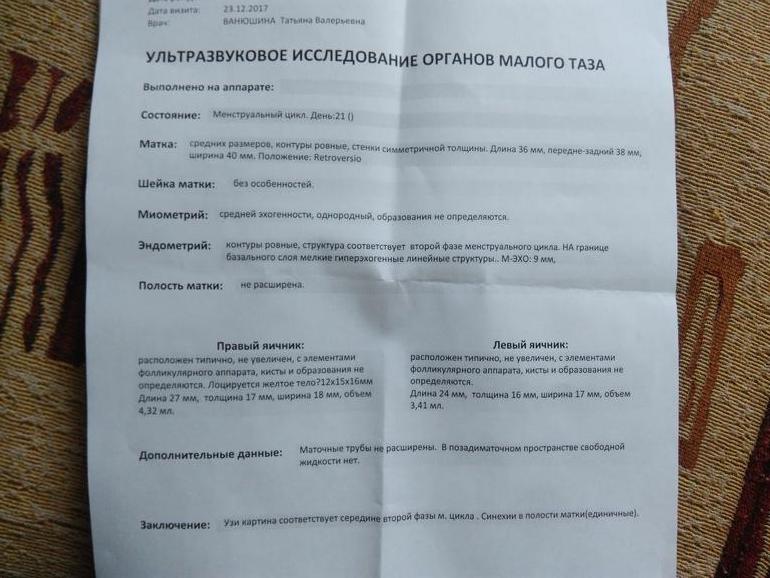

УЗИ на 5 дпо

После ОК решила сходить на УЗИ. Вот такая картина .

эндометриоз в матке спит, но единичные включения есть. Спросила, была ли овуляция, она говорит, вроде есть жт. Но померять базальную температуру, я вам точно не скажу. Капец а не узист. Я думаю, в ЛЯ есть жт. На снимке вроде оно. Хотя в заключении написано в правом яичнике жт под ?

эндометриоз в матке спит, но единичные включения есть. Спросила, была ли овуляция, она говорит, вроде есть жт. Но померять базальную температуру, я вам точно не скажу. Капец а не узист. Я думаю, в ЛЯ есть жт. На снимке вроде оно. Хотя в заключении написано в правом яичнике жт под ?